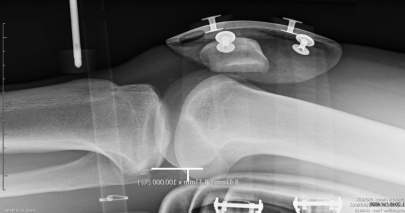

La Laximétrie Dynamique Automatisée, pour une approche nouvelle de l´examen de la fonction ligamentaire

La LDA® permet la mesure et le calcul de nouveaux paramètres pour faciliter un examen radiologique parfois difficile de la fonction ligamentaire du genou.

Le test de LDA® est le complément indispensable de l’imagerie médicale lors de l’exploration du LCA.

Le GNRB Radio dispose d’une fonction de blocage de 5 secondes en position haute du tiroir tibial, qui permet la prise d’un cliché radiographique.

Exemple donné: Contrôle préopératoire

Δ 134 = 6 mm, Δ P2 = 2

Rupture totale

Objectivation d’un test clinique de Lachman